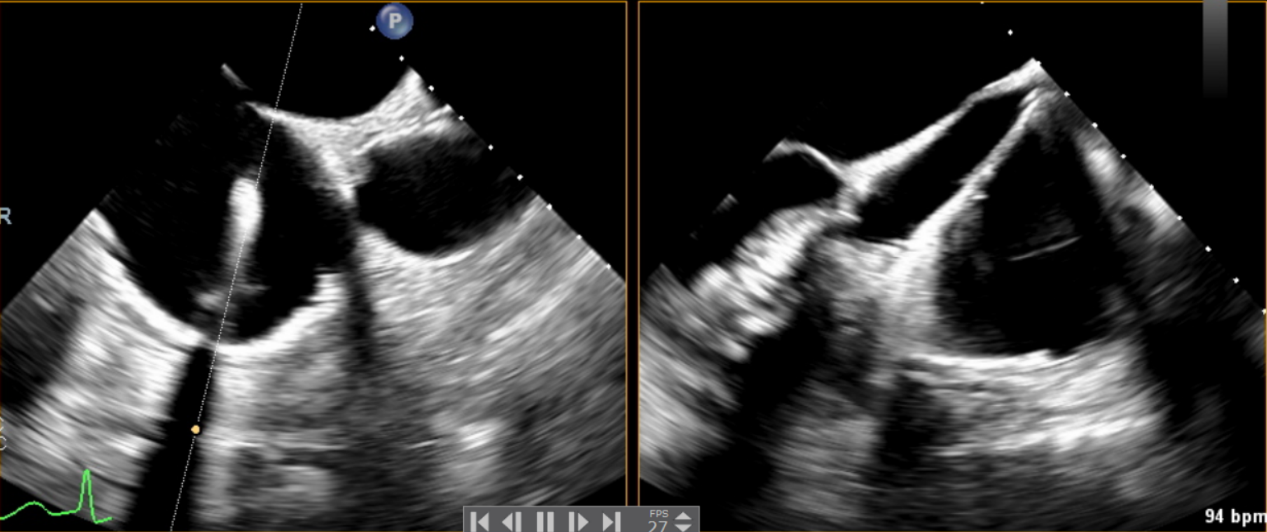

術前超聲提示大量三尖瓣反流

術中輸送器在超聲引導下調整位置